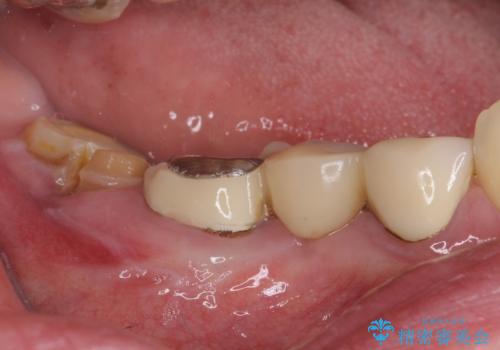

- 近医で奥歯が割れているので抜歯が必要と言われたとのことで来院された患者様です。

診断の結果、歯根が縦に破折しており抜歯が必要な状態でした。

抜歯してからインプラント埋入までには時間がかかるため、その間に下顎左右臼歯の金属のブリッジをオールセラミックへ変えていくこととしました。